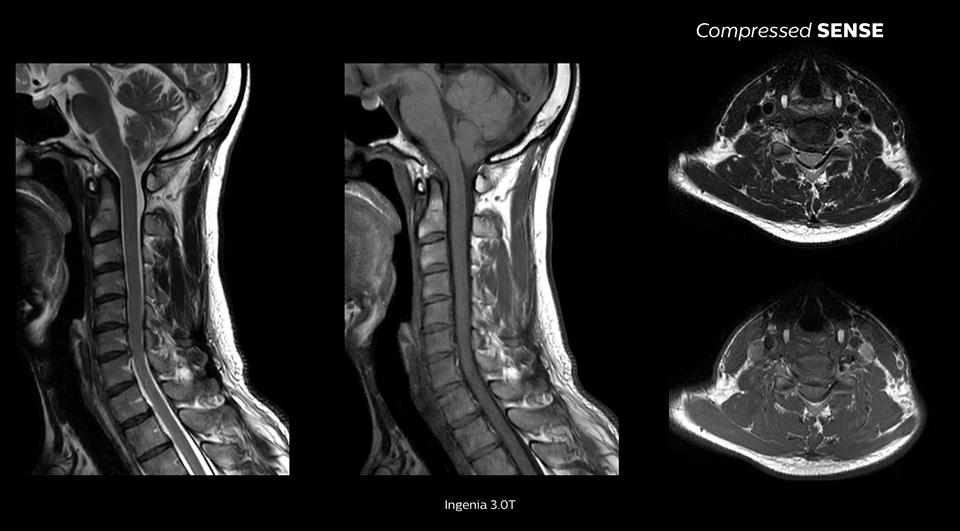

En passant de nos protocoles habituels à Compressed SENSE, nous avons constaté une réduction de 20 % de la durée d’acquisition. À la lecture des images, aucun des médecins n’est capable de dire s’il s’agit d’une acquisition obtenue avec ou sans Compressed SENSE."

Avec une qualité d’image pratiquement identique1

Jusqu’à 64 % d’amélioration de la résolution spatiale1